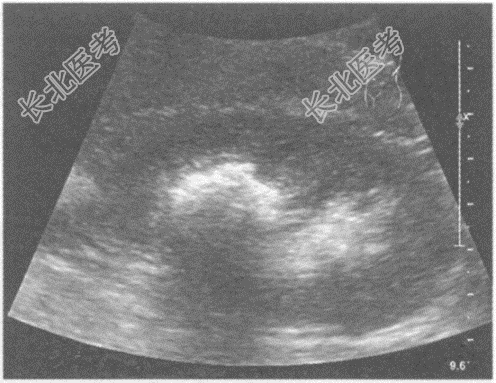

- 单项选择题临床资料:女, 25岁,因反复四肢麻痹10年, 腰部疼痛、肉眼血尿3月余入院。

化验检查:尿常规红细胞3+。

超声综合描述: 双肾形态、大小正常,沿肾锥体分布可见多个强回声光团, 后伴声影。

超声提示: A、双肾钙乳症

B、双肾海绵肾

C、双肾多发结石

D、双肾多发钙化

E、双肾错构瘤